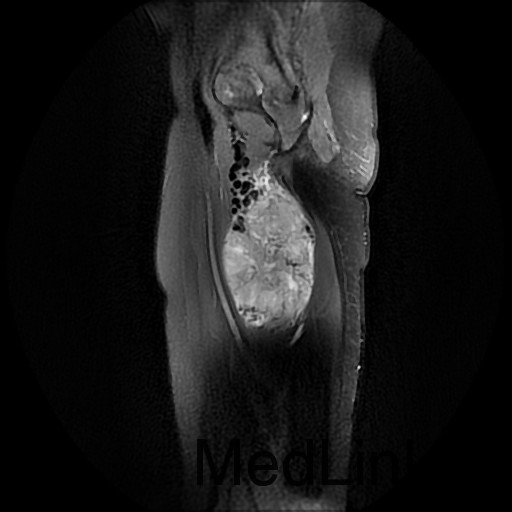

诊断:肺占位性病变(转移瘤?);大腿软组织疾患(右侧大腿肿物) 治疗:入院右下肢MR平扫+增强扫描:右侧大收肌软组织占位性病变,考虑间叶源性恶性肿瘤可能性大,血管源性可能?瘤周多发静脉曲张及侧枝循环形成,建议CT增强扫描进一步检查明确血管情况。遂于声引导下右大腿肿物穿刺活检,病理结果提示:(右大腿肿物)送检穿刺组织,肿瘤细胞形成器官样及腺泡状结构,细胞巢间为纤维性分隔,细胞呈大圆形、多边形,胞质丰富透亮,部分呈嗜伊红色,细胞核大,核分裂象少见,结合临床病史及免疫组化,考虑为腺泡状软组织肉瘤。免疫组化结果(①):CK(-),Vim(-),Ki-67(5%+),HMB45(-),MelanA(-),SMA(+),desmin(-),Myogenin(-),MyoD1(-),S100(-),NSE(部分+),CD56(-)。

1、 腺泡状软组织肉瘤:组织来源不明细胞呈腺泡样或器官样排列的软组织恶性肿瘤,称之为腺泡状软组织肉瘤。 2、好发于青春,女性多见,常位于四肢深部肌肉或筋膜,少数可见于腹壁,肛旁区,舌,腹膜后,颈背部,肿瘤生长缓慢,早期无痛,常偶然发现,大者直径可达6~10cm,瘤块虽增大不快,但血循丰富,浅表者可触及搏动。 3、治疗:原则上应施行肿瘤广泛切除术,边缘切除极易复发,此肿瘤对现行的化疗、放疗不敏感,疗效不肯定,